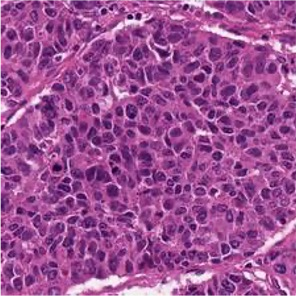

Multiple instance learning (MIL) is a powerful approach to classify whole slide images (WSIs) for diagnostic pathology. A fundamental challenge of MIL on WSI classification is to discover the \textit{critical instances} that trigger the bag label. However, previous methods are primarily designed under the independent and identical distribution hypothesis (\textit{i.i.d}), ignoring either the correlations between instances or heterogeneity of tumours. In this paper, we propose a novel multiplex-detection-based multiple instance learning (MDMIL) to tackle the issues above. Specifically, MDMIL is constructed by the internal query generation module (IQGM) and the multiplex detection module (MDM) and assisted by the memory-based contrastive loss during training. Firstly, IQGM gives the probability of instances and generates the internal query (IQ) for the subsequent MDM by aggregating highly reliable features after the distribution analysis. Secondly, the multiplex-detection cross-attention (MDCA) and multi-head self-attention (MHSA) in MDM cooperate to generate the final representations for the WSI. In this process, the IQ and trainable variational query (VQ) successfully build up the connections between instances and significantly improve the model's robustness toward heterogeneous tumours. At last, to further enforce constraints in the feature space and stabilize the training process, we adopt a memory-based contrastive loss, which is practicable for WSI classification even with a single sample as input in each iteration. We conduct experiments on three computational pathology datasets, e.g., CAMELYON16, TCGA-NSCLC, and TCGA-RCC datasets. The superior accuracy and AUC demonstrate the superiority of our proposed MDMIL over other state-of-the-art methods.